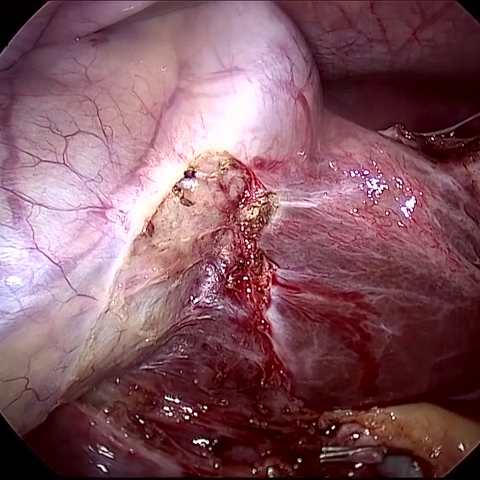

Refer to caption (a) Input Refer to caption (b) DIACMPN Refer to caption (c) Desmoke-LAP Refer to caption (d) PFAN Refer to caption (e) MITNET Refer to caption (f) Salazar Refer to caption (g) Dehamer Refer to caption (h) Ours Refer to caption (i) Target

Figure 3: Comparison of different methods on the LSD3K dataset.

IV-C2 Qualitative Analysis

Figures 3 and 2 provide a visual comparison of the desmoking results on challenging images from the test sets. The visual results corroborate our quantitative findings. DCP not only fails to remove the dense smoke but also introduces severe color distortion. CNN-based methods like FFA-Net and MSBDN successfully remove a large portion of the smoke but tend to either leave behind a thin layer of residual haze or over-smooth the image, losing critical textural details of the tissue and surgical instruments. The Transformer-based methods, DehazeFormer and PFAN, produce significantly better results by restoring more details. However, they can sometimes struggle with non-uniform smoke distribution, resulting in regions with unnatural brightness or minor artifacts.

In stark contrast, our RGA-Net generates visually superior results that are remarkably close to the ground-truth images. It effectively removes even the densest plumes of smoke while simultaneously preserving fine-grained details, such as blood vessels, tissue textures, and reflections on surgical tools. Furthermore, the color and illumination of the restored scene appear more natural and consistent, which is a direct benefit of our model’s ability to handle both local and global features through its hybrid attention and cross-gating mechanisms. This enhanced visual clarity is crucial for improving the surgeon-robot interface in real-world clinical applications.